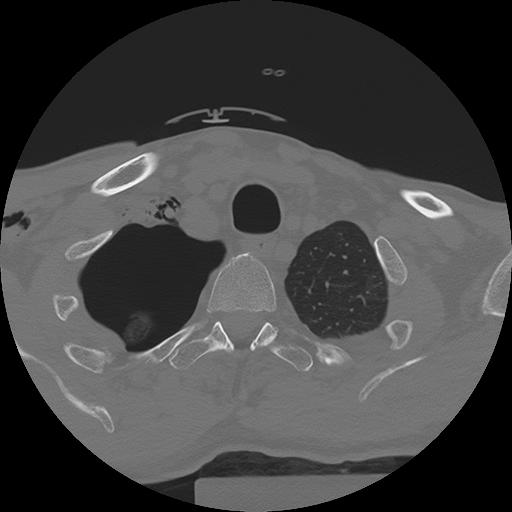

11 HUESO,,Axial,2.0,HUESO,,